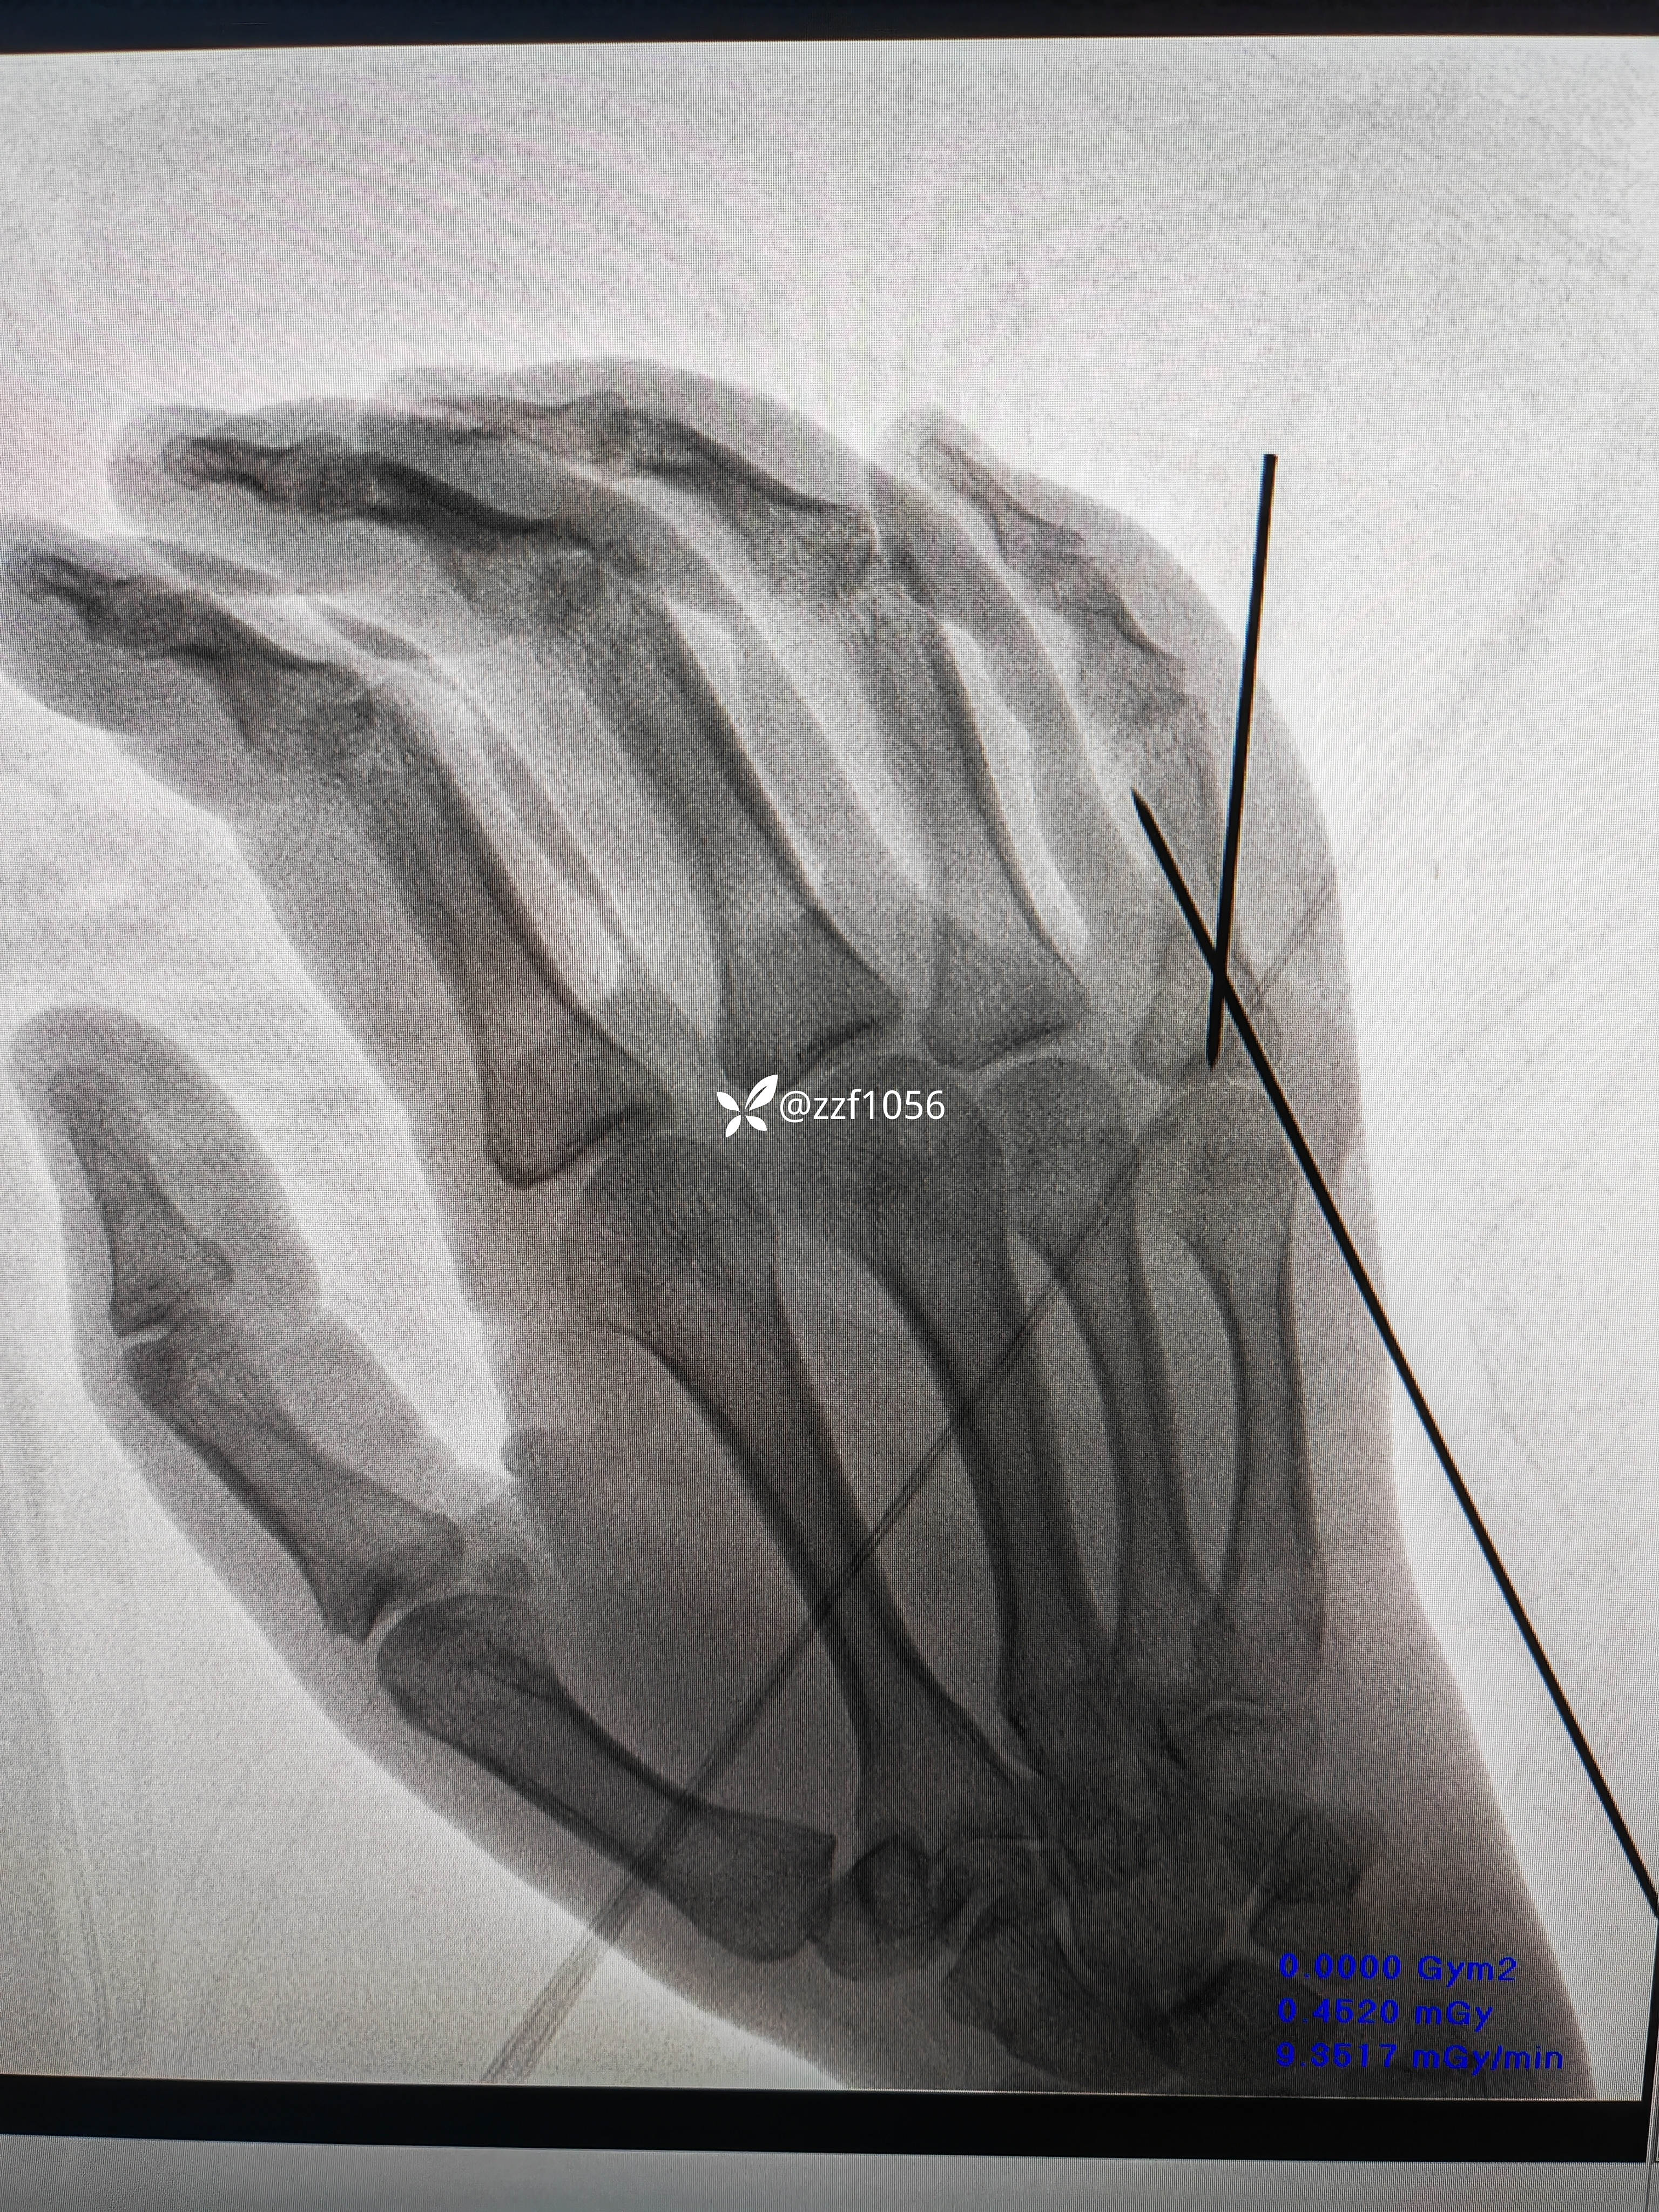

15:10分消毒铺巾准备台上行腕部神经阻滞麻醉,手法整复直接经皮交叉穿针,术中透视并调整,处理针尾,术中活动良好克氏针稳定;

看看术中效果

15:30走出手术室返回病房。

患者和家属看到术中视频后非常满意